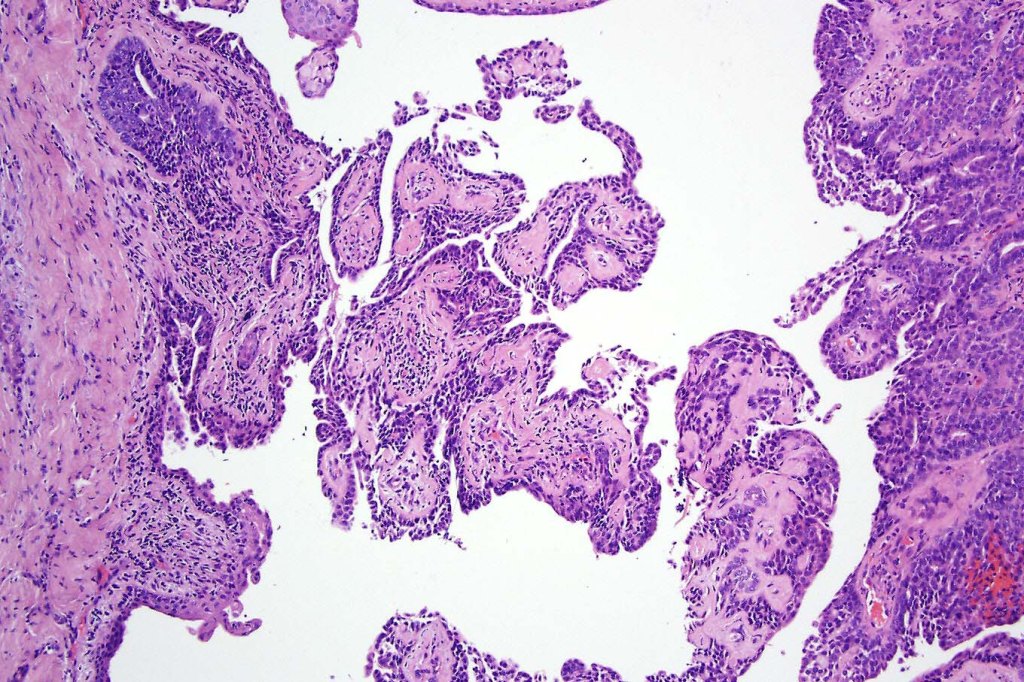

Histological features

•Papillary component (may include pseuopapillae & true papillae with a fibrovascular core)

•Back-to-back glands with double-layered epithelium

•Cuboidal/columnar with eosinophilic cytoplasm & vesicular nuclei

•Variable clear cell change & foci of squamous differentiation

•Variable pleomorphism & mitotic activity (can appear deceptively bland)

In the majority of cases, digital papillary adenocarcinoma is easily recognised even at scanning magnification. Very exceptionally, a metastasis from a visceral papillary carcinoma must be excluded. Clinicopathological correlation should resolve the matter. Where doubt remains, identification of a myoepithelial layer and CK7 expression will confirm the diagnosis. Some cases can appear deceptively bland and papillary eccrine adenoma may have to be excluded. Again clinicopathological correlation is valuable as is the identification of true papillae, nuclear pleommorpism and excessive mitotic activity.